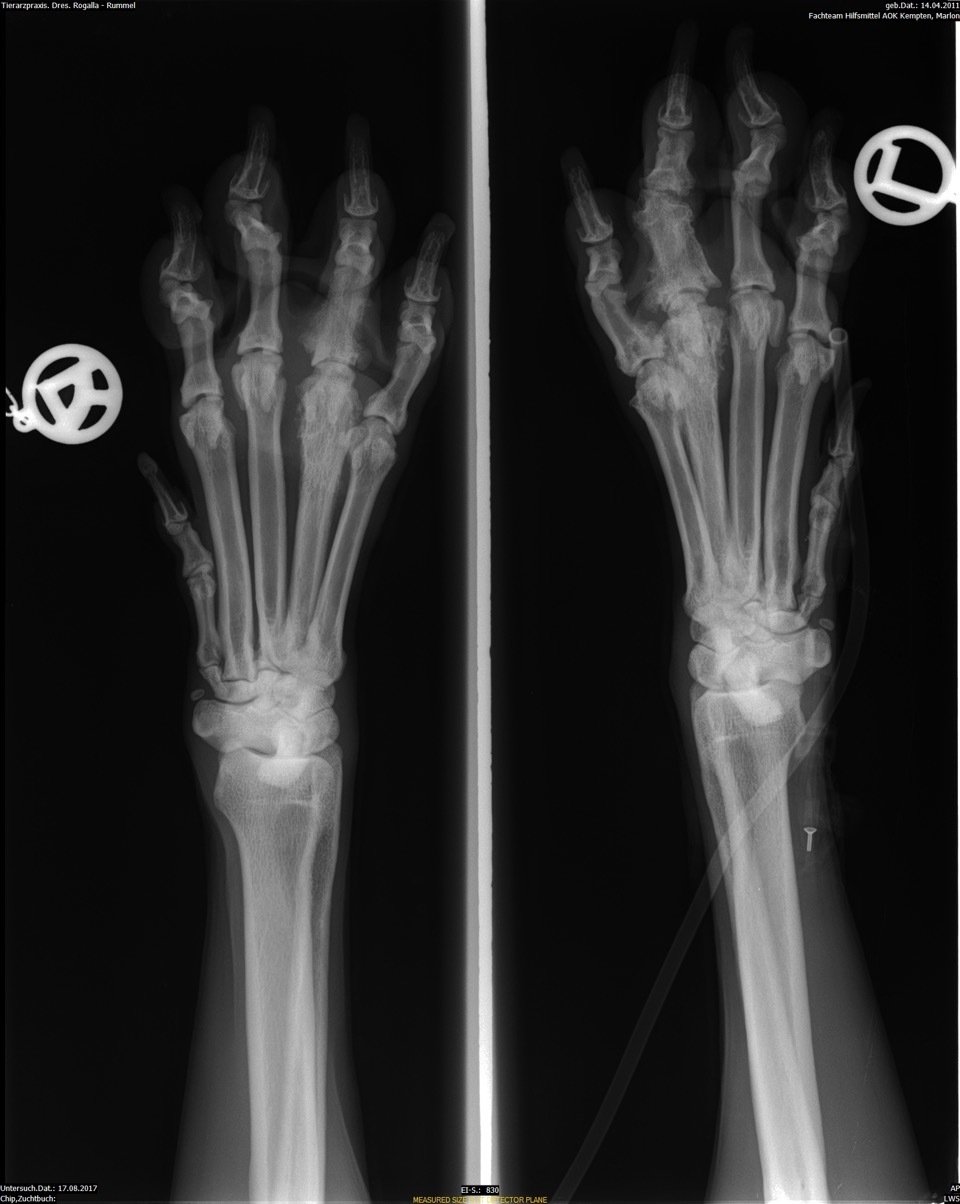

In Narkose wurden Ellbogen, Schulter und Pfoten beidseitig geröntgt. Wie schon vermutet, lag das Problem nicht am Ellbogen, vielmehr waren die Zehengelenke der linken Pfote arthrotisch verändert (Polyarthrose). Ich wählte für Marlon jetzt ganz besondere Akupunkturpunkte aus, um seine Schmerzen zu nehmen. Mit einem kleinen Trokar wurden die Goldbits in diese Punkte implantiert, (funktioniert ähnlich wie das Setzen eines Mikrochips) - die kleinen Einstichstellen verheilten schnell.